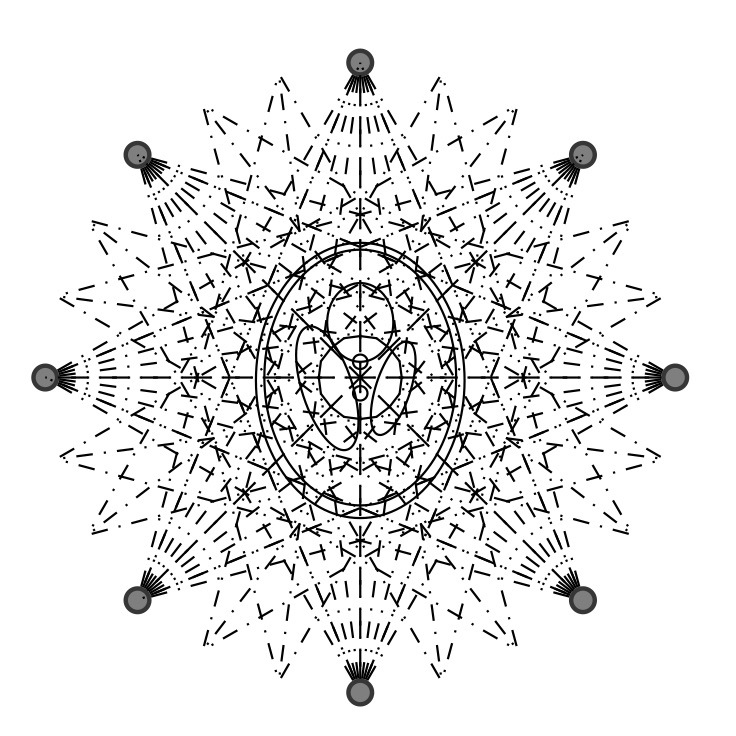

where is the number of photons scattered in the volume unit and is the electron density. As depicted by Figure 1, the number of photons scattered from an incident beam of flux in the volume element within a solid angle oriented by is calculated by differentiating eq. 5.

We assume to measure a total of photons and compute synthetic data from eq. 11 for a phantom electron density modeling a transversal slice of a human thorax. The phantom (see fig. 2(b)) consists of characteristic functions of ellipses of different sizes and opacities and is a modified version of an earlier phantom which was used in [12]. It is 28.4 cm resp. 21.3 cm wide at its largest and smallest diameters and its gray values are chosen as electron densities of materials typical in a human thorax [15, 3, 30].

As was mentioned in the description of the reconstruction algorithm, the procedure is carried out with a very small number of source and detector positions. This is enabled by the energy as additional dimension of information in the CST step. Assume a setup with 16 angular views, see Figure 7 for 8 angular views. For every angle, the radiation behind the object is measured by 32 detectors distributed equidistantly around a half circle opposite to the source. Particularly, note that this setup is an instance of the geometry assumed in the Sobolev mapping results Theorems 3.10 and 3.12. Regarding the radiation source, we assume a total emission intensity of photons per viewing angle and an initial photon energy level of MeV. The detectors measure radiation at 256 energy levels in the range MeV to MeV, leading to a necessary energy resolution keV. The nature of the source is incorporated in the simulation of the data by computing Poisson distributed values .